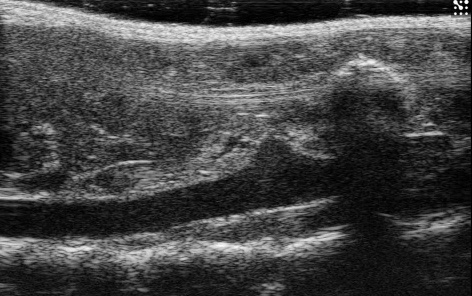

Simulated inference

Browser mock · real B-mode frame

Mimics the real Mask R-CNN inference on a B-mode frame from the rat aorta dataset. The red overlay is a browser mock, not model output.